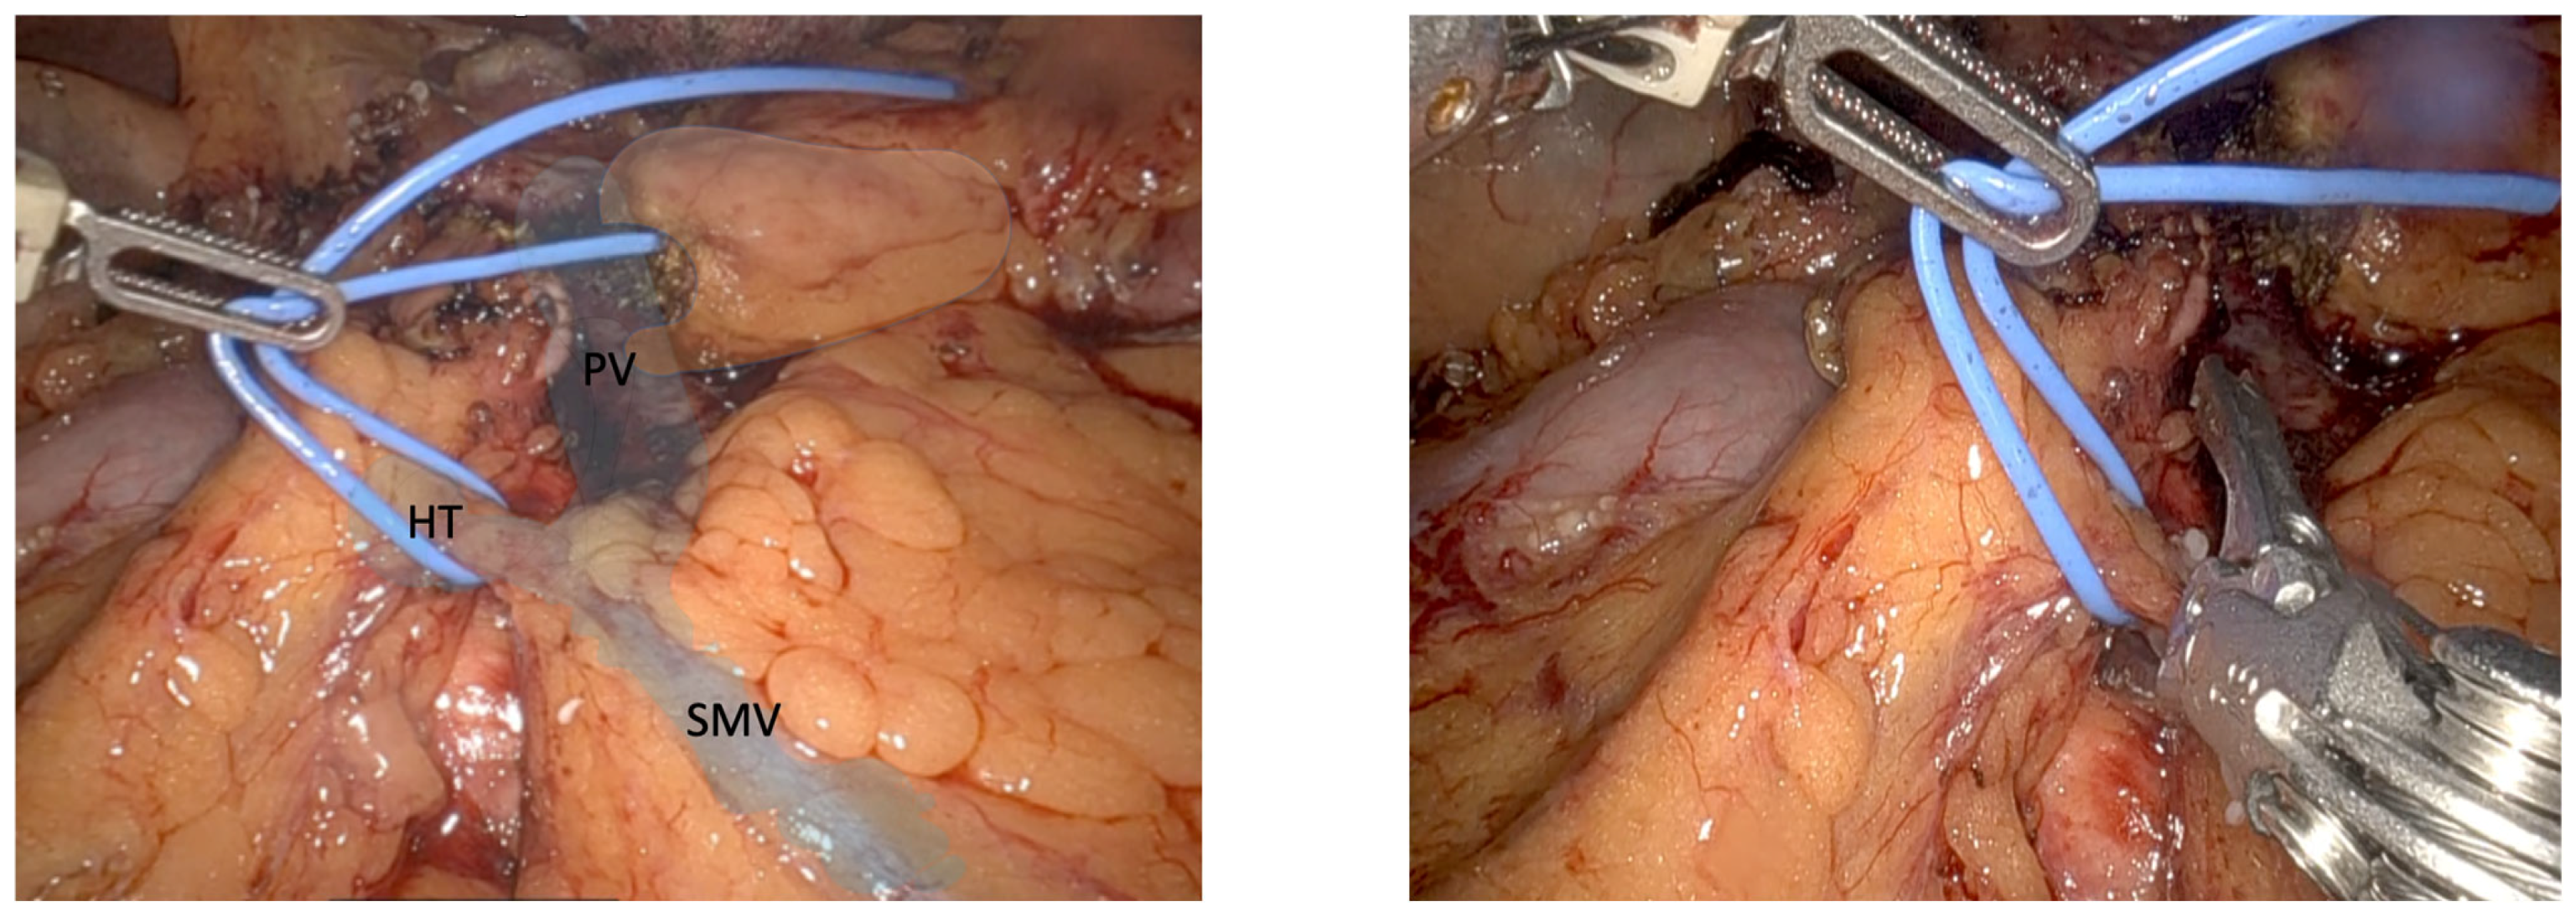

Identified during the pancreatic head dissection, this vein is a consistent main tributary of the PV, making it a major landmark for dissection of the uncinate process. BV is present in 90% of patients [7,9,10]. It joins the right posterolateral wall of the PV, usually within 1 cm from the splenic vein–portal vein confluence [7]. BV transection should be performed using polymer locking or a metal clip (see Figure 3), allowing the broad and safe exposure of the PV and SMV and thereby opening the posterior hilar portal confluence, helping to complete the 360° PV dissection, before ending the pancreas head mobilization. Ideally, BV transection should be postponed until all SMA branches have been transected to prevent venous congestion in the pancreatic head.

On the other hand, the BV is a valuable anatomical landmark during the final step of dissection of the uncinate process (see Figure 3). Once the TH has been taken, the uncinate process begins to detach from the SMV-PV axis. As BV arises in a posterolateral position, it may be unintentionally injured during dissection if the surgeon is not aware of it. This is why its proper identification and control enables the final step of the uncinate process dissection to be performed without significant incidental bleeding, but at the same time, allows the possibility of dissecting the PV in 360° and completing the radical hilar lymphadenectomy with precision and vascular control.

Figure 3. The posterosuperior pancreaticoduodenal vein, also referred to as Belcher’s Vein, is isolated using a vessel loop. A polymer locking clip is applied to achieve vascular control. The portal vein (PV), superior mesenteric vein (SMV), and Belcher’s Vein (BV) and P (Pancreas)are identified.